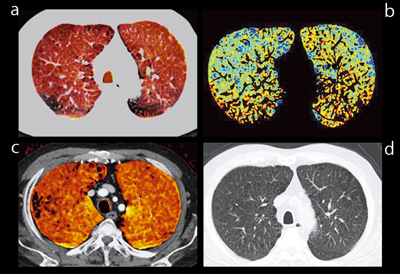

●症例2:CPFE(図7)

単純CT(図7d)でもデンシティが高く,線維症であることがわかるが,parenchyma画像(図7b)でも線状の赤い表示が多数認められ,線維化が明瞭に認められる。また,Xeの欠損域(図7a,c)では血流が保たれており,肺気腫とは異なるCPFEの特徴が見て取れる。

図8に,症例2のコロナル画像を示す。

![]() 図7 症例2:CPFE(72歳,男性),下肺野,アキシャル画像 a:Xeイメージ b:parenchyma画像 c:Lung PBV d:単純CT画像 |